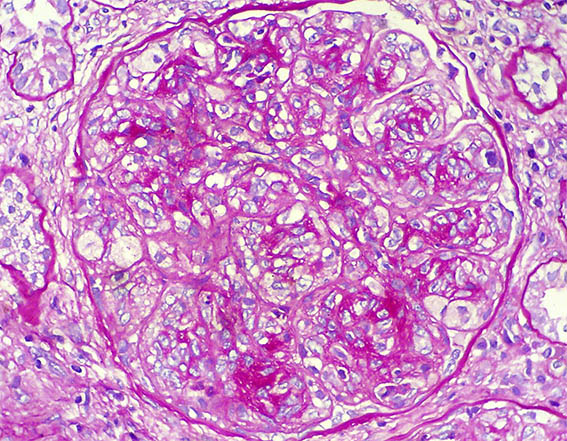

A renal biopsy was done, see the images.

Figure 4. PAS, X400.